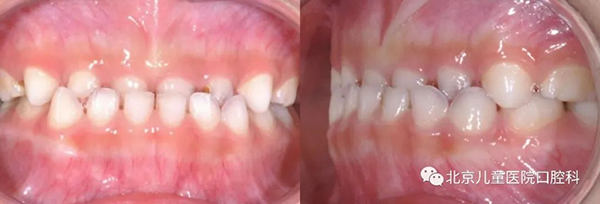

一、乳牙期(3-5岁)

这个阶段主要是针对“地包天”的矫正和口腔不良习惯(吮指、咬唇、吐舌、口呼吸等)的破除,以利颌骨的发育,预防更严重错合的发生。

牙齿“地包天”,咬合时下前牙在上前牙外面